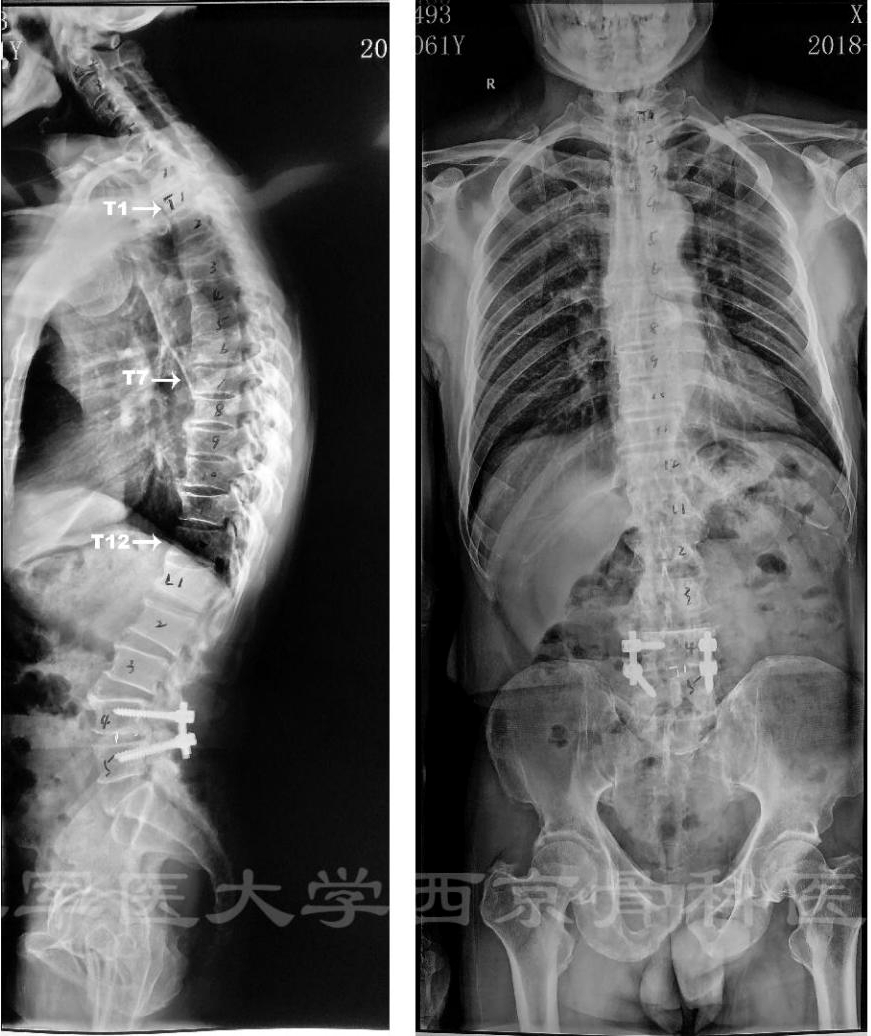

术前X线正侧位片

术前MRI